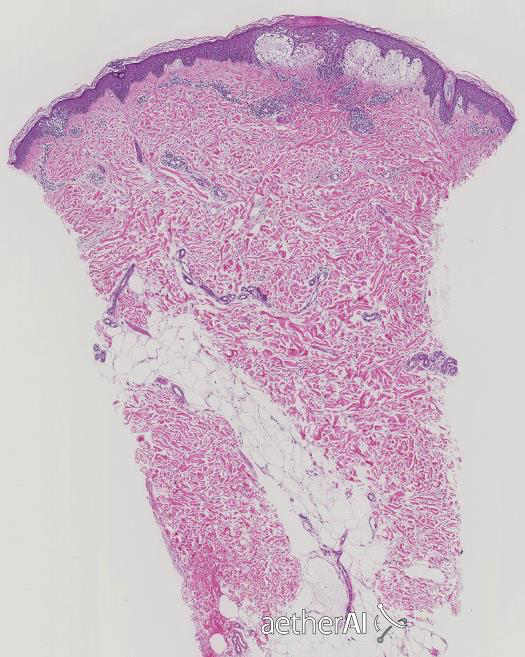

scarring or non-scarring?

NON-SCARRING ALOPECIA * Preserved Sebaceous Glands * Absence of destructive inflammation or fibrosis around the follicles